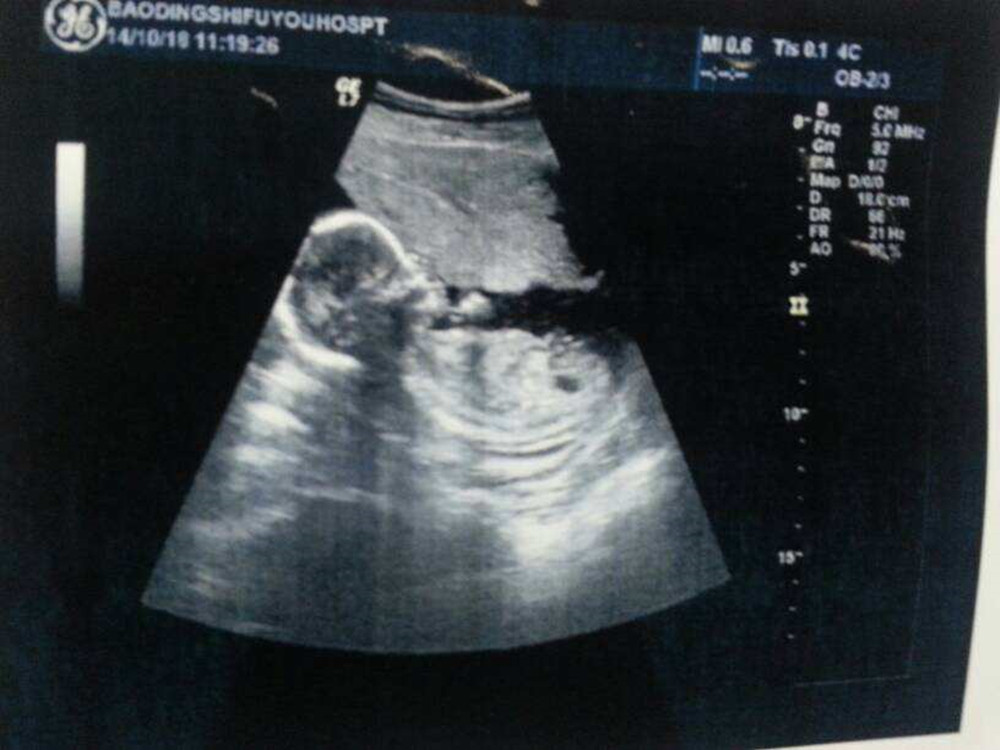

菁菁怀孕24周之后,胎动更加明显了。其实她大女儿已经3岁了,这是二胎。因为第一次怀孕时稀里糊涂的,对胎动、产检都没啥经验,反倒是这次非常上心。

这一胎总是在左边胎动,而且感觉力量还不小呢!身边老人都说,这一胎准保是个男孩子。听到这些话语,准妈高兴极了,赶上胎动明显时还会录下来,留作纪念。